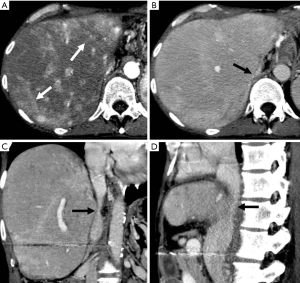

Changes of parenchymal enhancement in the liver and spleen

Reversed portal flow shunting of arterial contrast caused by HAPS leads to decreased splenic enhancement and increased hepatic enhancement on HAP images (Figure 4). Therefore, (I) the enhancement of the liver is significant, while that of the spleen is decreased during the HAP; and (II) the density (signal intensity) of the liver is close to or even higher than that of the spleen.